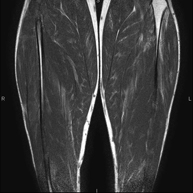

Exploración ideal para el estudio de lesiones en músculos isquiotibiales y cuadriceps, frecuentemente lesionados en deportistas. También permite una buena valoración de tendones y nervios periféricos. Tiene una duración aproximada de 20 minutos. No emplea radiación ionizante. - RM Rodilla

Exploración para el estudio de lesiones en tendones, músculos y nervios periféricos. De gran utilidad para el diagnóstico de las roturas fibrilares en gemelos. Tiene una duración aproximada de 18 minutos. No emplea radiación ionizante. - RM Tobillo

Prueba diagnóstica no invasiva que consiste en la obtención de imágenes de alta definición anatómica de la musculatura a estudio mediante el empleo de un campo electromagnético y ondas de radio (con un emisor y un receptor). No utiliza radiación ionizante. En escasas ocasiones se requiere el uso de contraste paramagnético (Gadolinio) para mejor definición de las lesiones. - RM Huesos y articulaciones